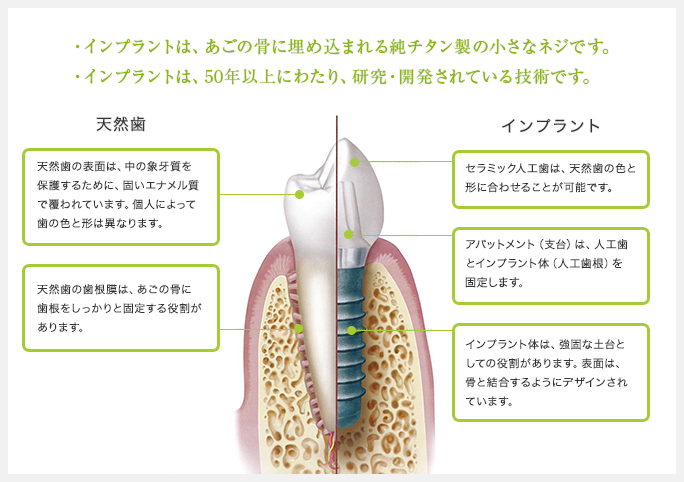

インプラントとは、歯が抜けてしまった部分へチタン製の人工歯根を埋め込み、その上に人工歯を取り付ける治療法です。

インプラントの構造

- インプラント治療は、チタンでできた人工歯根(インプラント体)を骨の中に埋め込み、その上に歯を再現する治療方法です。自然で違和感が少ないのがインプラント治療の特徴です。自然の歯と同じように食事がとれます。

- インプラント体は、フィクスチヤーと呼ばれる人工の根の部分と、アバットメントと呼ばれる土台の部分と、クラウンという被せ物の3構造から成ります。クラウンの部分が壊れてしまった場合は、修復可能ですが、その他の部位が壊れてしまった場合は、再手術が必要となります。